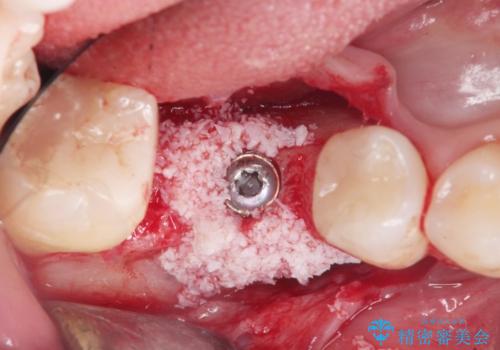

骨の増成を含むインプラント治療を計画します。

安定し、長く使用できるようなインプラント治療を実践するため、骨の増成をインプラント埋入と同時に行いました。